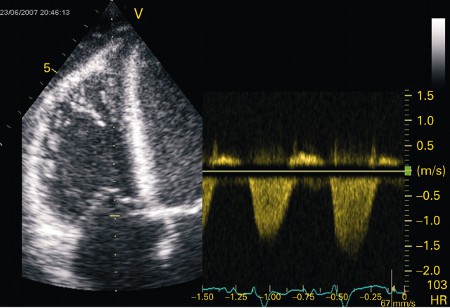

Apical 4-chamber transthoracic echocardiogram in a patient with myocarditis. The right ventricle is dilated with hypokinesis. Triscupid regurgitation is present with a reduced continuous wave Doppler gradient indicating right ventricular failure

From: Rasmussen TB, Dalager S, Andersen NH, et al. BMJ Case Reports 2009; doi:10.1136/bcr.09.2008.0997